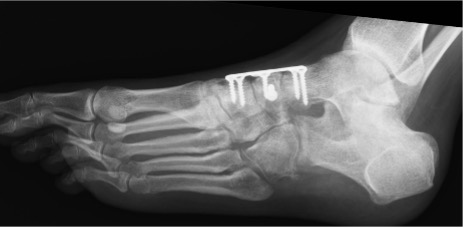

- Consider longitudinal skin incisions and longitudinal plates (Figure 9)

- Caution with the use of circumferential anatomical plate given radial nature of blood supply (Figure 10)

Figure 9: Interfragmentary lag screw and bridge plating of a crushed navicular

Figure 10: Example of circumferential plating of a comminuted navicular fracture without lag screws; robust attention to preserving the medial column; late collapse of the navicular can be seen